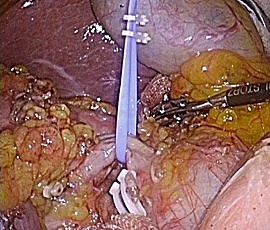

腹腔鏡下結腸・直腸切除術の実際

全身麻酔下で手術を行います。まず腹腔内(腹腔:お腹の壁と臓器との間の空間のことで

す)に炭酸ガスを入れて膨らませ、お臍からカメラ(腹腔鏡)を挿入します。この際、同

時に手、術操作に用いる器具(鉗子など)を挿入するために、5〜10mmの小さな穴を左

右に4ケ所開けます。そして腹腔鏡で撮ったお腹のなかの様子をモニターに映し出して、

大腸切除や周囲のリンパ節の切除を行います。開腹手術では見えにくかった細かい血管

や神経まで見えて繊細な手術操作が可能です。実際の腹腔鏡手術は、開腹手術と同じ全

身麻酔下で行います。

この手術は、専用の高性能カメラからの拡大した鮮明な画像を見ながら行うため従来の、

開腹手術では見えにくかった部位や細かい血管・神経まで見えて繊細な手術操作が可能

です。腹腔内で操作を終えたあとに最後に臍切開創を4−5cmに延長し病変をお腹の外

に取りだします。

結腸切除術の場合は体外で、直腸切除術の場合は体内で吻合(腸と腸をつなぐ)を行いま

す。特に直腸がんの場合、肛門温存術に関しては、非常に肛門に近くて従来なら永久人

工肛門となっていた超低位の直腸がんに対しても肛門縁から2〜3cmほど距離があって

一定の条件を充たせば、永久人工肛門を極力避けて自分の肛門を残す超低位直腸切除術

を積極的に行っています。